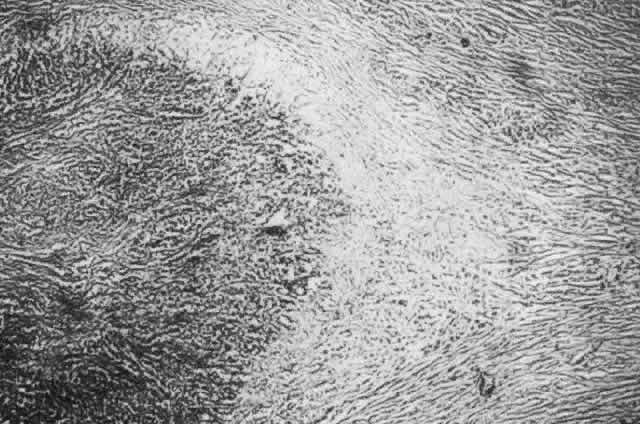

collagen remote from the site of cellular infiltration.  Fig. 21. Advancing edge of a granulomatous reaction. Scleral fibers are split and

separated by edema and then disrupted when invaded by the granuloma Fig. 21. Advancing edge of a granulomatous reaction. Scleral fibers are split and

separated by edema and then disrupted when invaded by the granuloma

|